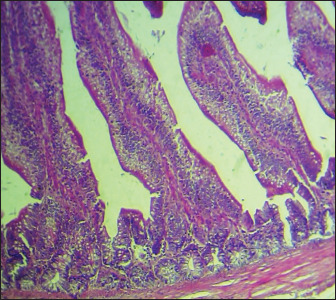

Results: The obtained results showed that broilers that were infected with S. enteritidis and given curcumin and C. myxia did better in terms of body weight, IgG, and IgA levels than the positive untreated group. In particular, C. myxia was better than curcumin in IgA. Even though curcumin or mixed therapy raised glutathione, it also decreased the number of heterophils (heterophilia) and inflammatory cytokines (IL-8 and TNF-α). This happened because the number of white blood cells and lymphocytes was reduced in the groups that got curcumin or C. myxa. The number of goblet cells also was raised. The intestinal villi stayed the same.